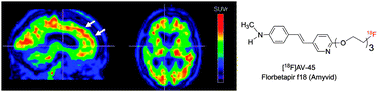

Single photon emission computed tomography (SPECT) or positron emission computed tomography (PET) imaging agents for neurodegenerative diseases have a significant impact on clinical diagnosis and patient care. The examples of Parkinson's Disease (PD) and Alzheimer's Disease (AD) imaging agents described in this paper provide a general view on how imaging agents, i.e. radioactive drugs, are selected, chemically prepared and applied in humans. Imaging the living human brain can provide unique information on the pathology and progression of neurodegenerative diseases, such as AD and PD. The imaging method will also facilitate preclinical and clinical trials of new drugs offering specific information related to drug binding sites in the brain. In the future, chemists will continue to play important roles in identifying specific targets, synthesizing target-specific probes for screening and ultimately testing them by in vitro and in vivo assays.